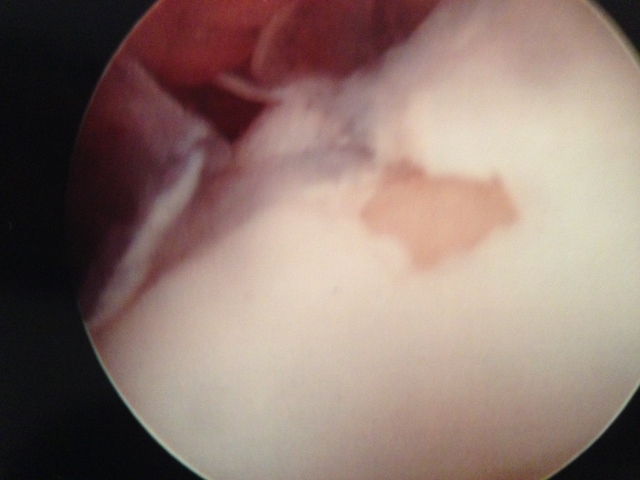

Pic of one of the nodules inside the ankle joint.

Pic of an OCD in the talar dome due to pressure from the nodule.